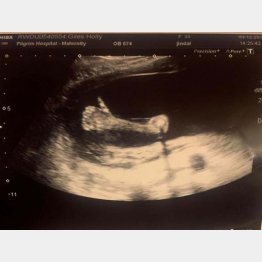

あやかりたい!赤ちゃんがママのお腹の中でサムズアップ

妊娠20週目を迎えたホリー・ガイルズさん(33)が妊婦検診で受けた超音波画像に、なんと赤ちゃんが親指を立てた「サムズアップ」が撮れていたのだ。サムズアップは国によって侮辱を表すこともあるが、英米や日…